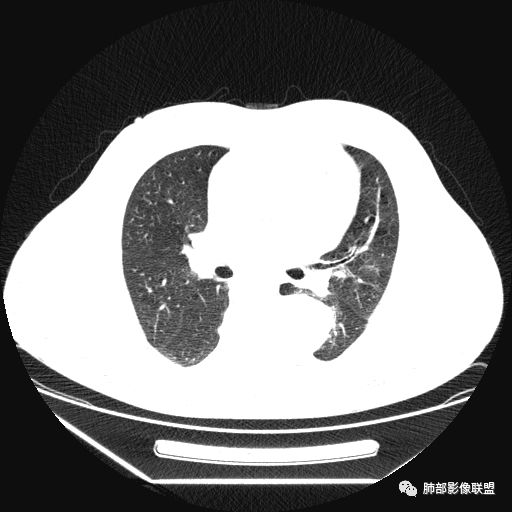

曹志勇:右肺尖后段类圆形病灶,边界清边,缘锐利,宽基底与胸膜相连,环形强化,内似见蛇纹血管征,考虑胸膜孤立性纤维瘤,右肺外底段病灶,考虑炎性可能大

红日东升:左侧胸椎旁肿块,边缘清晰光整,冠状位见D字征,未见支气管进入,肺组织受压表现,定位肺外。轻度强化,密度稍不均匀,临近肋骨变细,未见肺动脉供血,考虑良性肿瘤,神经源性可能。右肺下叶病灶,轻度强化,血管显影,边缘平直、凹陷,考虑炎性病变。

左肺下叶脊柱旁病灶,可见胸膜尾征,均匀强化,临近椎间孔未见扩大,考虑孤立纤维瘤,鉴别诊断神经源性肿瘤,右肺下叶病灶边缘平直,明显均匀强化,边缘清楚,考虑机化性肺炎。

张帅:患者中年男性,咳嗽 咳痰3月,痰为白色粘痰,左上肺病灶,边缘光滑,周围未见毛刺 分叶,肺组织受挤压,与胸膜关系密切,部分层面与胸膜脂肪间隙消失,有胸膜尾征,病灶定位于胸膜,病灶增强可见强化,边缘可见增强血管,内可见低密度区,考虑 孤立胸膜纤维瘤?神经鞘瘤?右肺下叶外基底段病灶,病灶与胸膜有牵拉,病灶边缘光滑,平直 u型征,未见明显毛刺,增强病灶内可见增强血管影,边缘低密度,考虑病灶内存在痰栓。右下肺病灶考虑良性炎症性病灶,ABPA?

张立:左侧胸椎旁肿块,边缘清晰光整,冠状位见D字征,未见支气管进入,肺组织受压表现,定位肺外。轻度强化,密度稍不均匀,,未见肺动脉供血,神经源性肿瘤,节细胞神经瘤可能。右肺下叶病灶,轻度强化,血管显影,边缘平直、凹陷,TB可能。

可芸:定位:肺外病变,胸椎旁肿块,边缘清晰光整,可见胸膜尾征无支气管进入,肺组织受压。轻度强化,密度稍不均匀,未见肺动脉供血,考虑良性肿瘤,神经源性,孤立性纤维瘤?右肺下叶病灶,轻度强化,血管显影,边缘平直、凹陷,炎性病变。

1.左上胸内脊柱旁半圆形肿块,质地坚实,密度比较均匀。

2.病灶周边见胸膜掀起,应当考虑胸壁或是纵隔来源,肺内病变不会如此。

3.降主动脉这一相对固定结构向前方推移,提示病灶相对坚实且有牢固附着点,不支持来自柔软的肺组织。

就如同在腹部,能将肾脏推移的包块,应该来自腹膜后。

4.可疑肋间动脉病供血,提示肿块来自后纵隔的可能性。

5.相邻椎间孔未见扩大,也未见块影延入椎管,易起自于神经根的鞘瘤似乎找不到相关支持点。

6.未提供矢状位骨窗图像,如在肋骨内下缘观察到压迹有助于肋间神经的鞘瘤的判断,这是因为二者之间密切的毗邻关系。

7.静脉期轻度强化,注意不是环形强化,亦未显示明确的“AB区”,神经鞘瘤与副节瘤亦未找到支持点。

综上,病灶定位胸壁或后纵隔,就发病率而言,神经源性可能性较大。